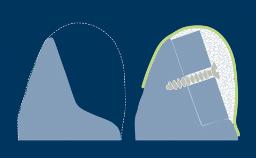

- descrever os fatores necessários para avaliar o osso na região do implante

- determinar a necessidade de aumento ósseo na região do implante